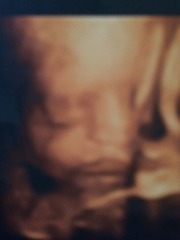

Had my 4d scan yesterday at 27 weeks!

This is my beautiful girl. Looks very like her father already, she has his nose and wee features. And also his long legs! They're 13.6cm long already, and she weighs around 2.4lbs.

12 weeks tomorrow and she'll be here ??